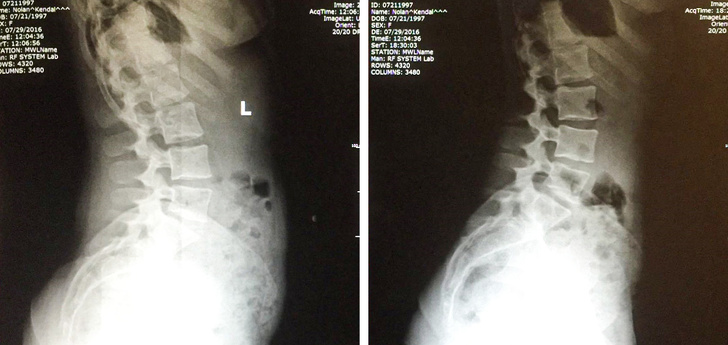

«Всього один місяць правильного харчування, і в результаті зменшилися обсяги і навантаження на хребет».